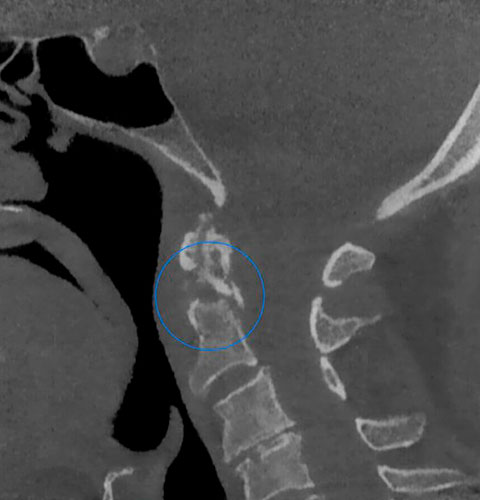

Veja exemplos de diagnósticos de imagem